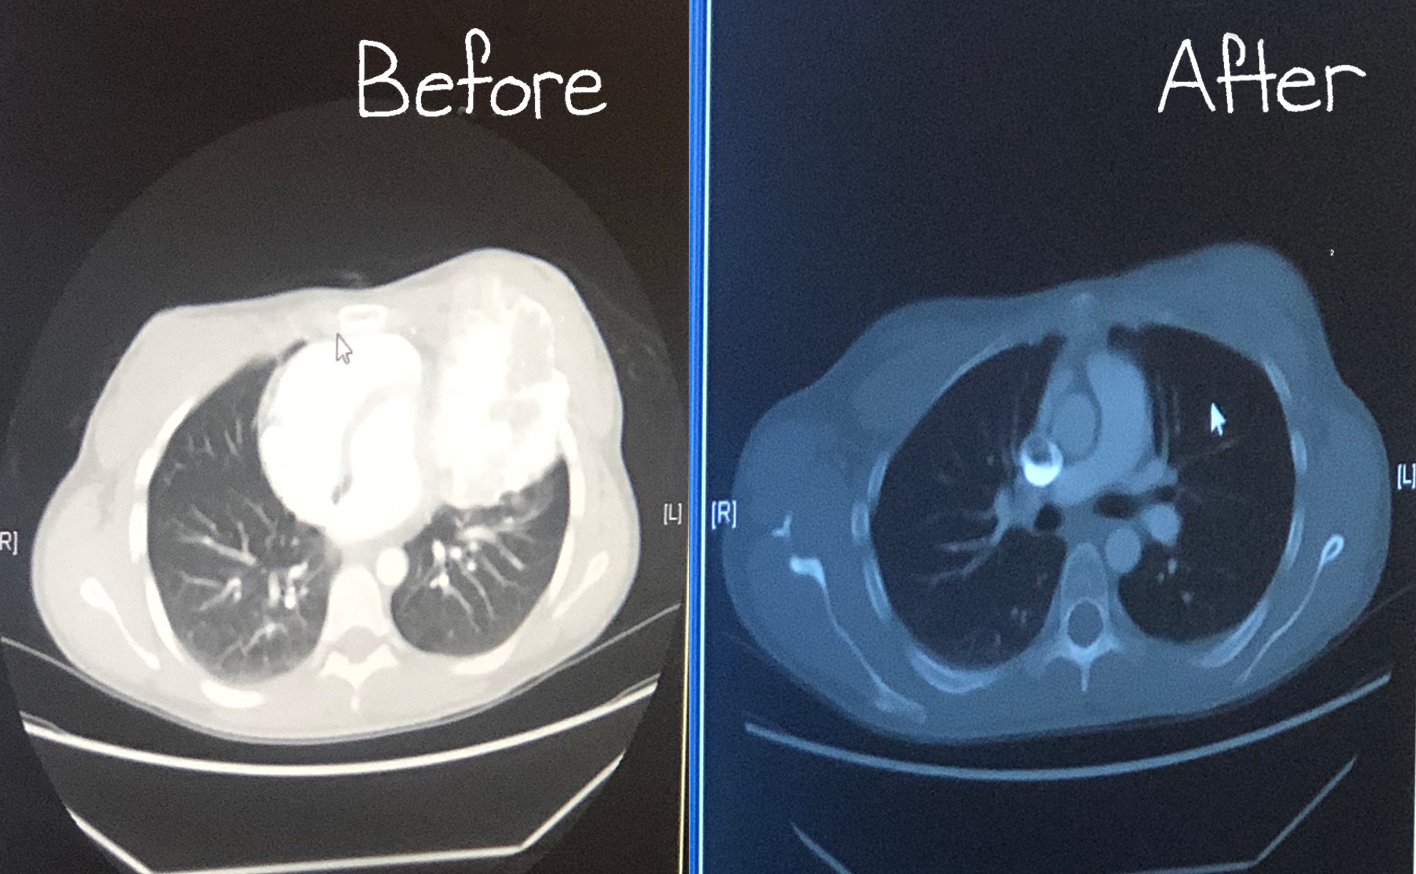

TUMOR

5" bone tumor removed from ribs in 2019